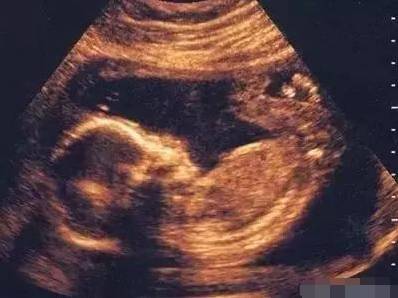

男性胎儿会在母亲子宫里勃起

大多数妈妈都不喜欢讨论这个话题,但不少争论的事实是许多男婴在子宫里都会犯错。研讨发现,男女婴儿在子宫内都可能有手淫的举措,超声波图像也曾抓拍到男婴的勃起图片。不过只有男性能在X光片上看出来,原因嘛…你们懂的。